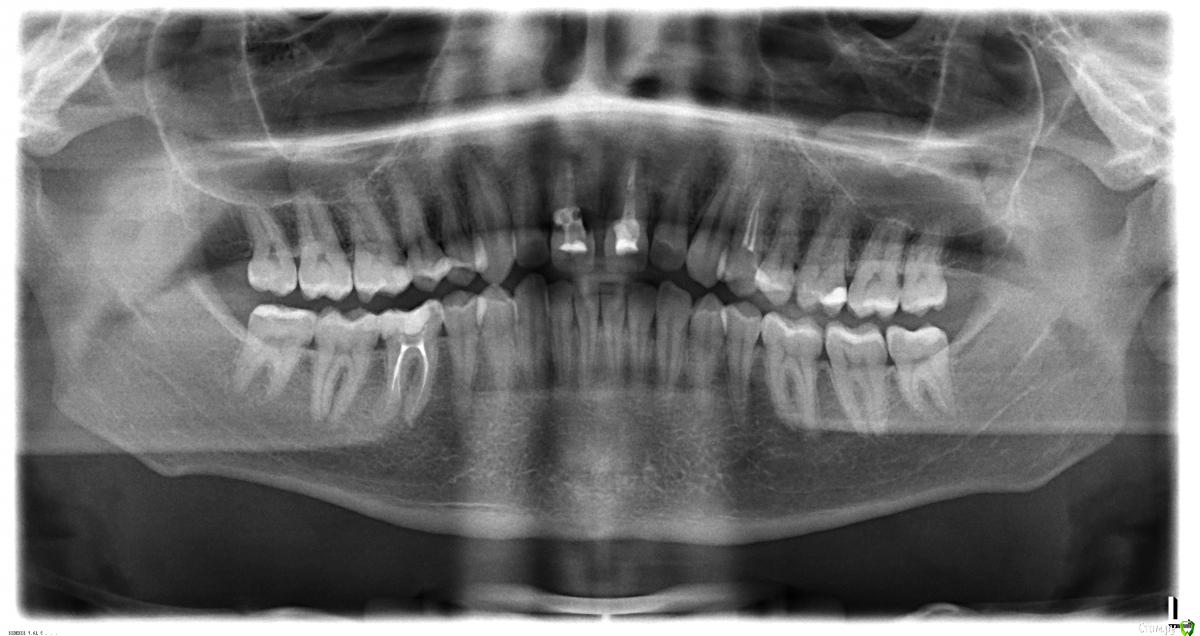

Alex397 Опубликовано 16 февраля, 2015 Поделиться Опубликовано 16 февраля, 2015 Здравствуйте! Подскажите пожалуйста по след. ситуации.Стоматолог сказал что два верхних резца требуют немедленного лечения каналов с последующей установкой коронок на оба зуба. Вопрос следующий: стоит ли устанавливать коронку на левый резец после лечения канала? Стоматолог аргументирует это тем, что это не зуб, а скорлупа и что он в любой момент может под основание отколоться и что потом спасти будет нельзя. Как вы считаете, есть ли такая необходимость? Ссылка на комментарий

SDC Опубликовано 16 февраля, 2015 Поделиться Опубликовано 16 февраля, 2015 На левый центральный резец может быть и стоит сделать коронку, но это второстепенный вопрос.Первично стоит рассмотреть вопрос удаления правого центрального резца с замещением имплантатом и коронкой по причине наружной резорбции/кариеса корня 11 зуба 4 Ссылка на комментарий

red_butler Опубликовано 17 февраля, 2015 Поделиться Опубликовано 17 февраля, 2015 делайте Кт, заодно посмотрим верхнечелюстные синусы 1 Ссылка на комментарий